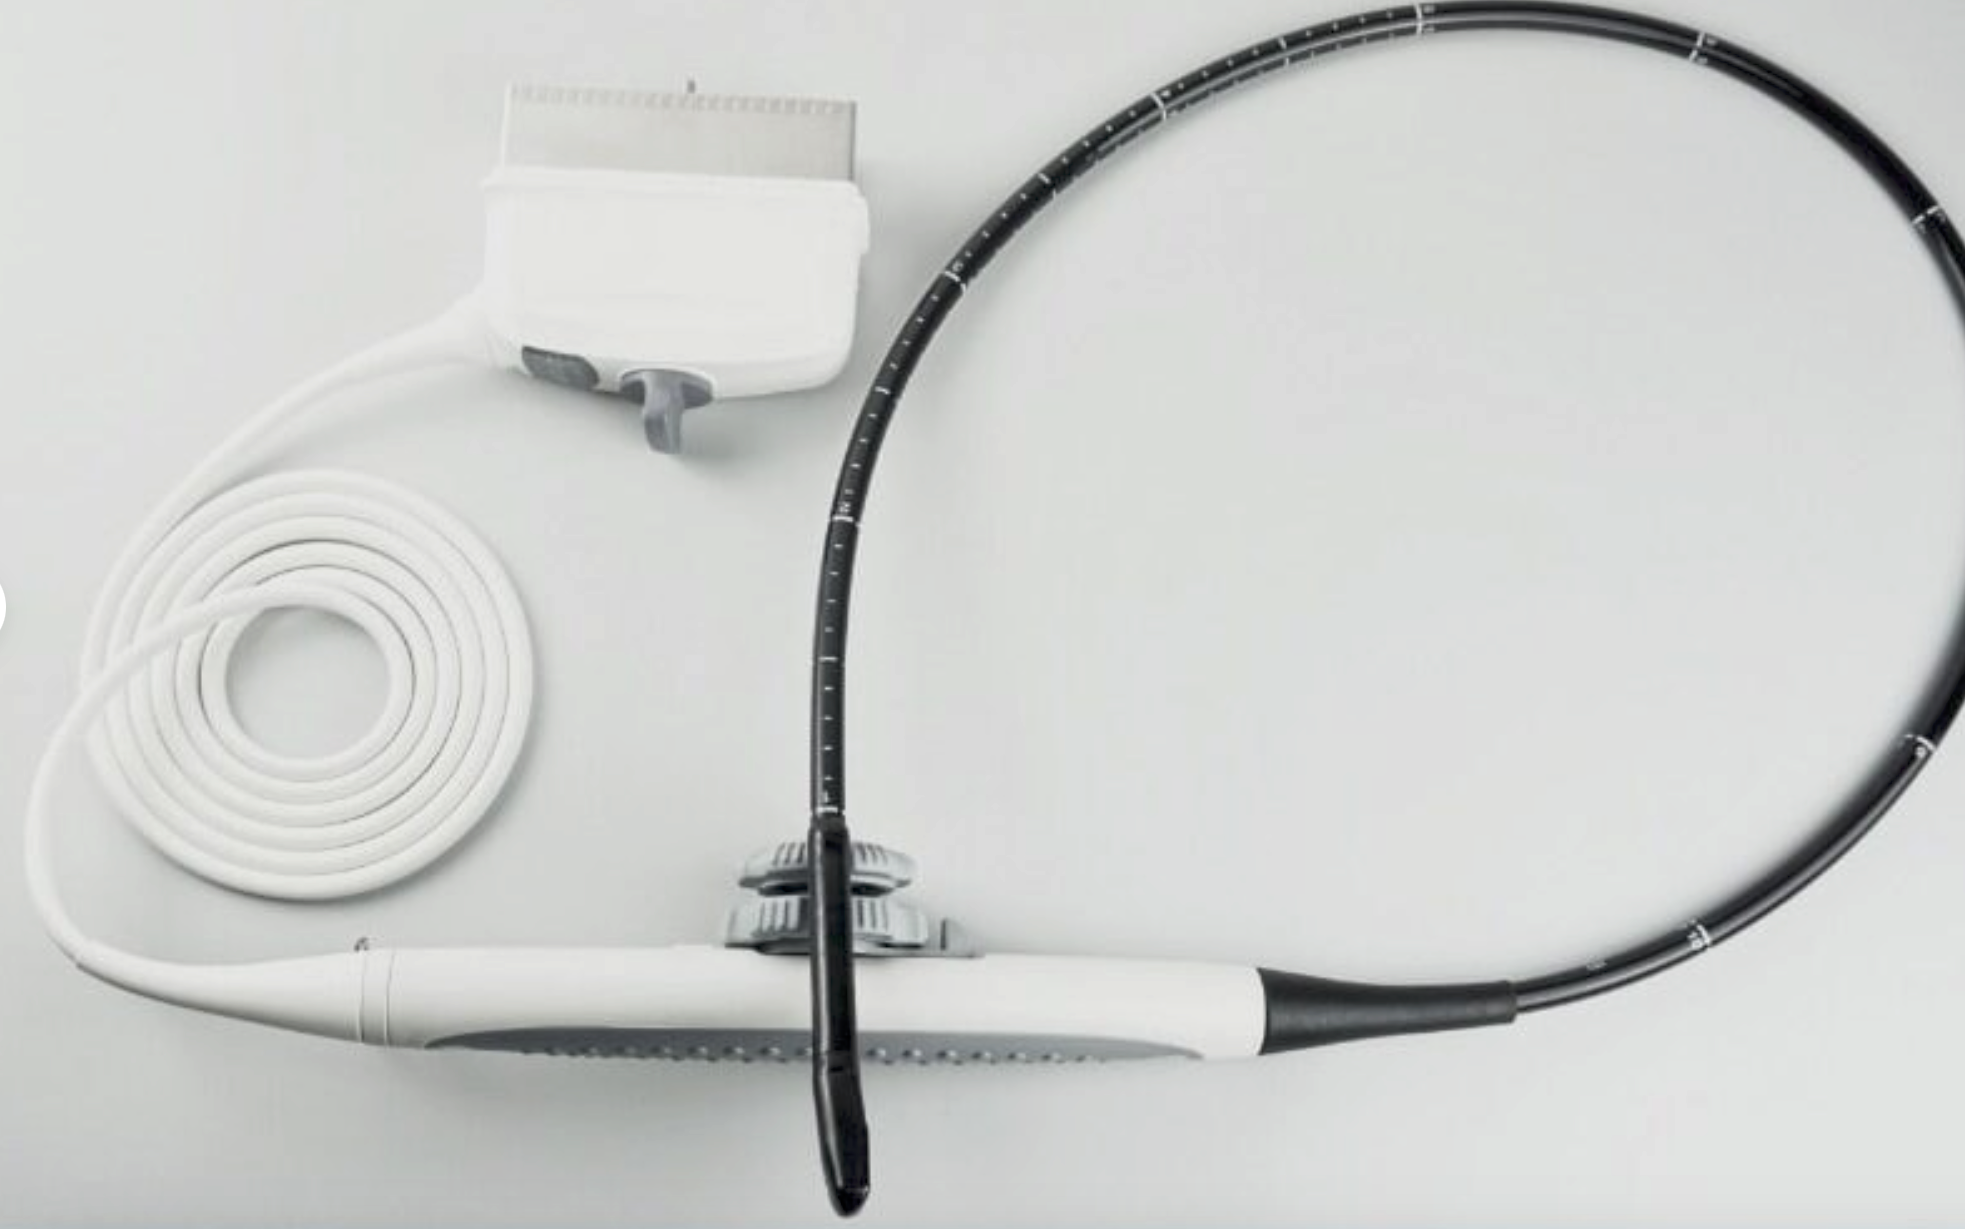

Probe Function: 3.5MHZ convex, abdominal organs

Probe 2: 7.5MHZ Transvaginal probe:gynecologic examination